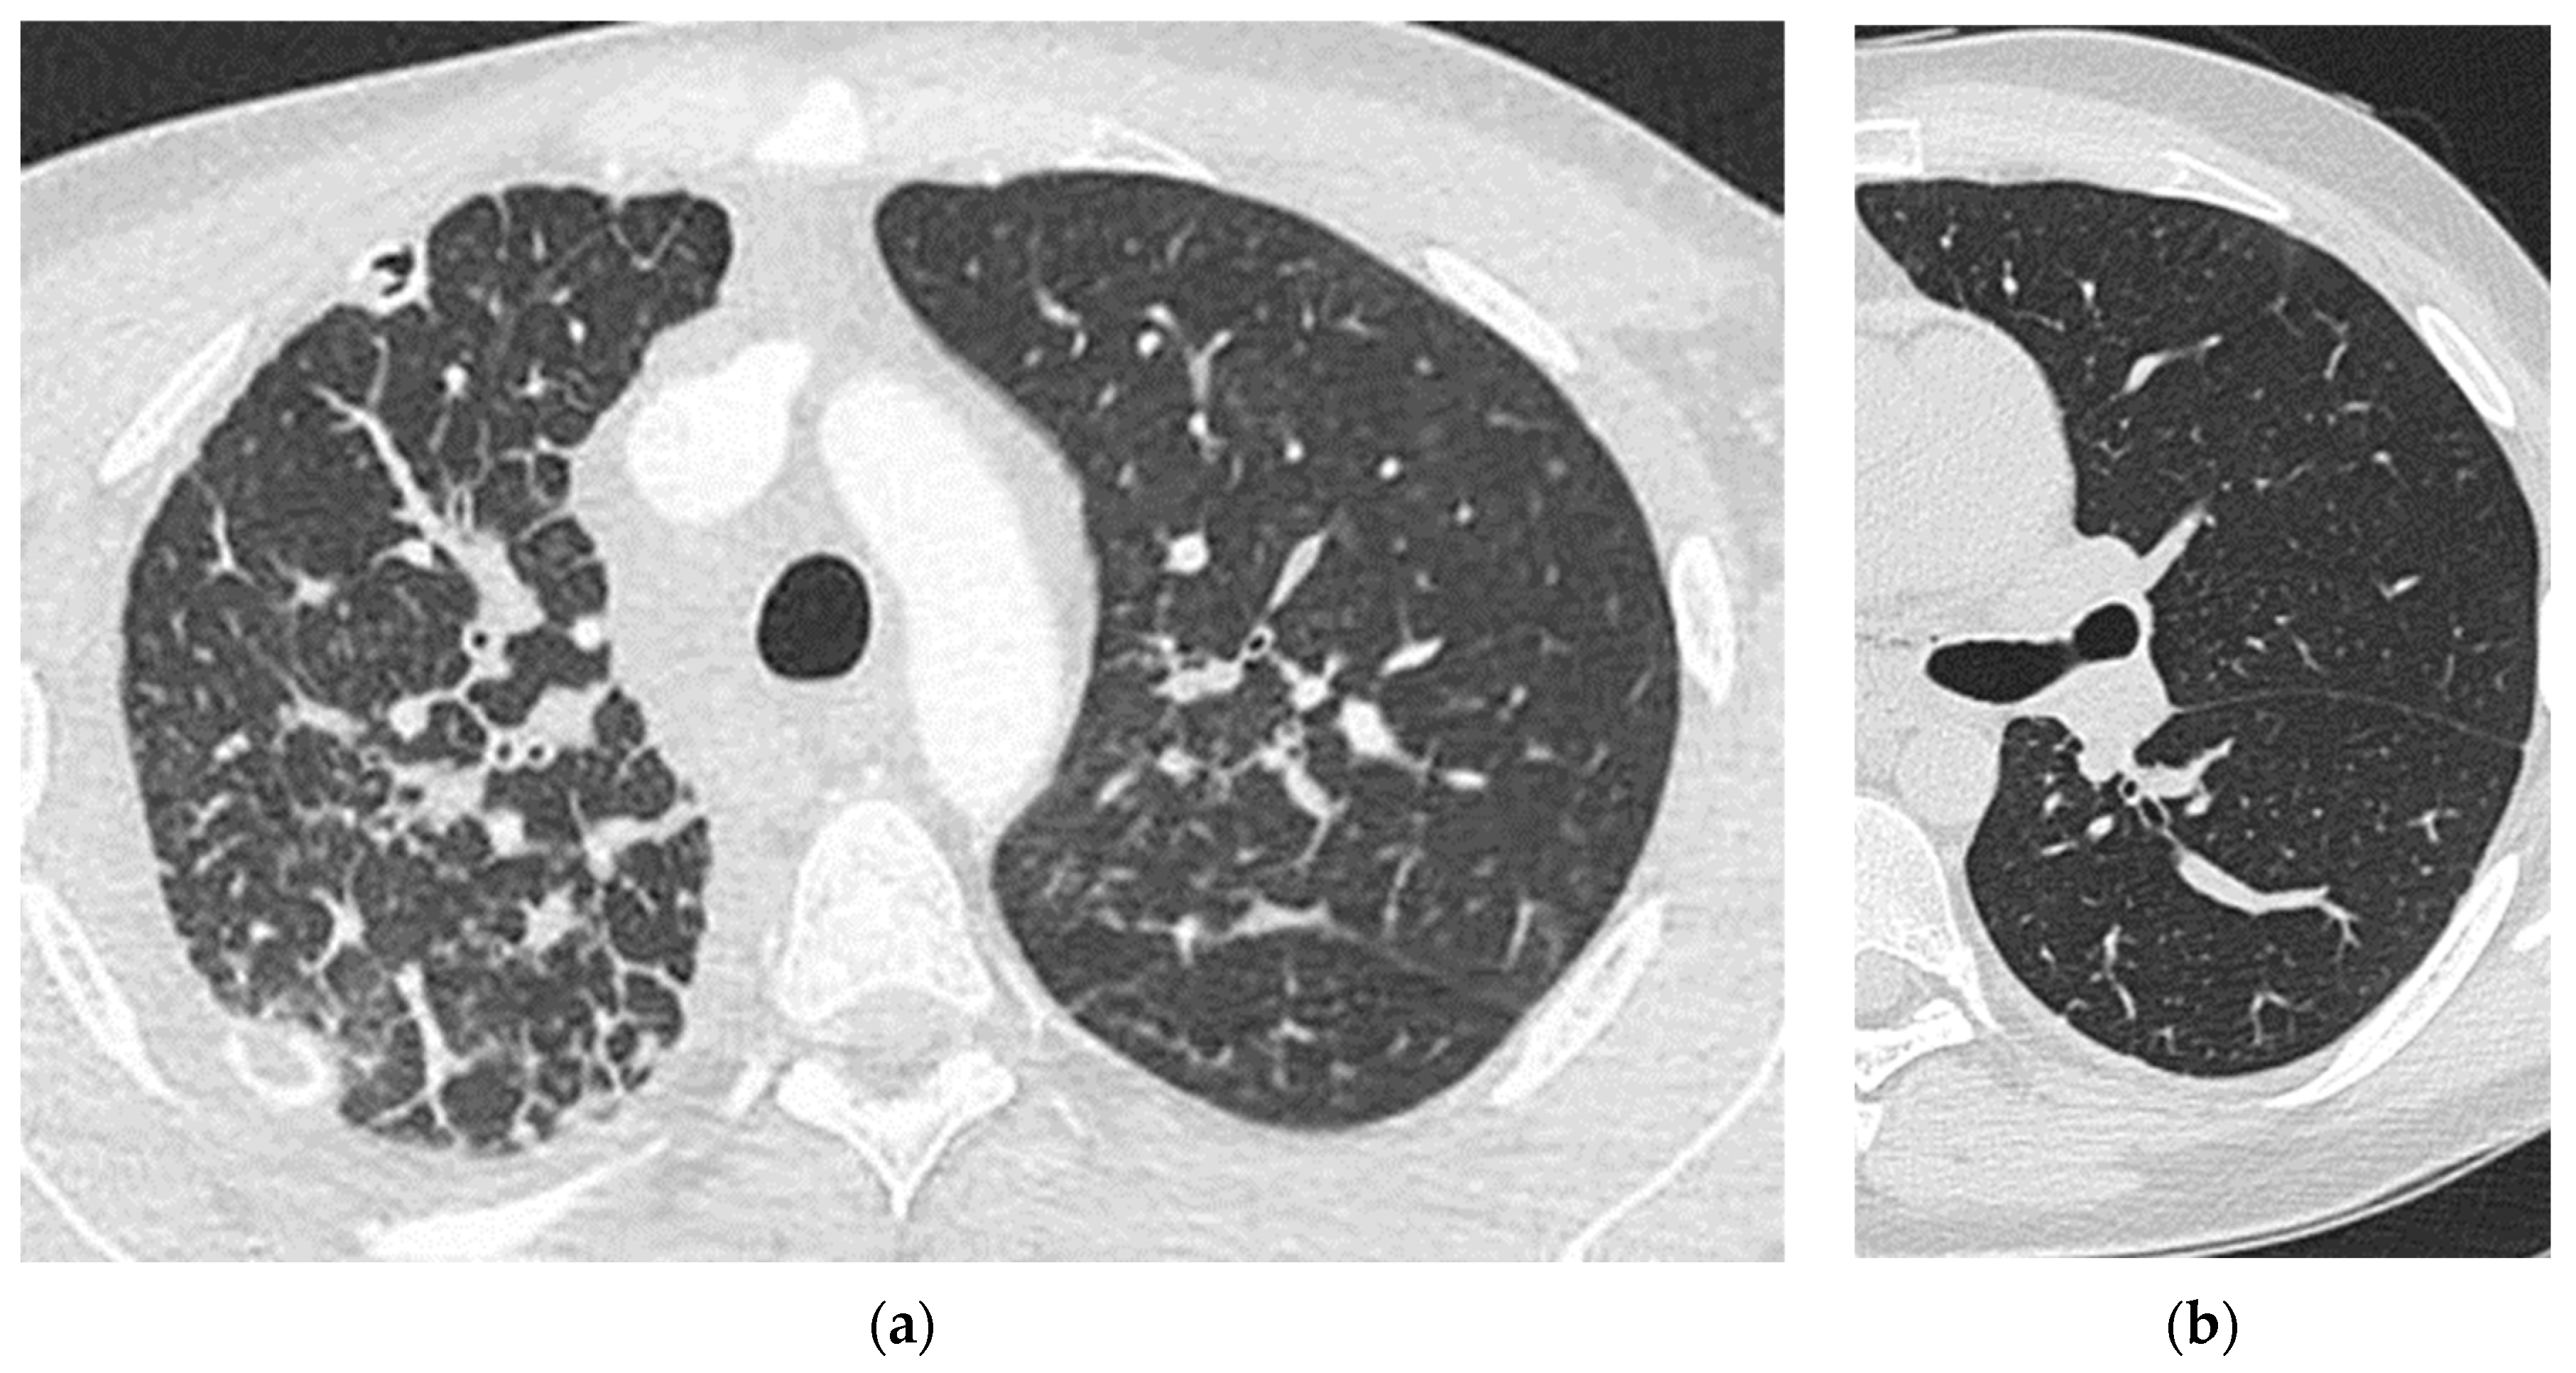

2. Case Report